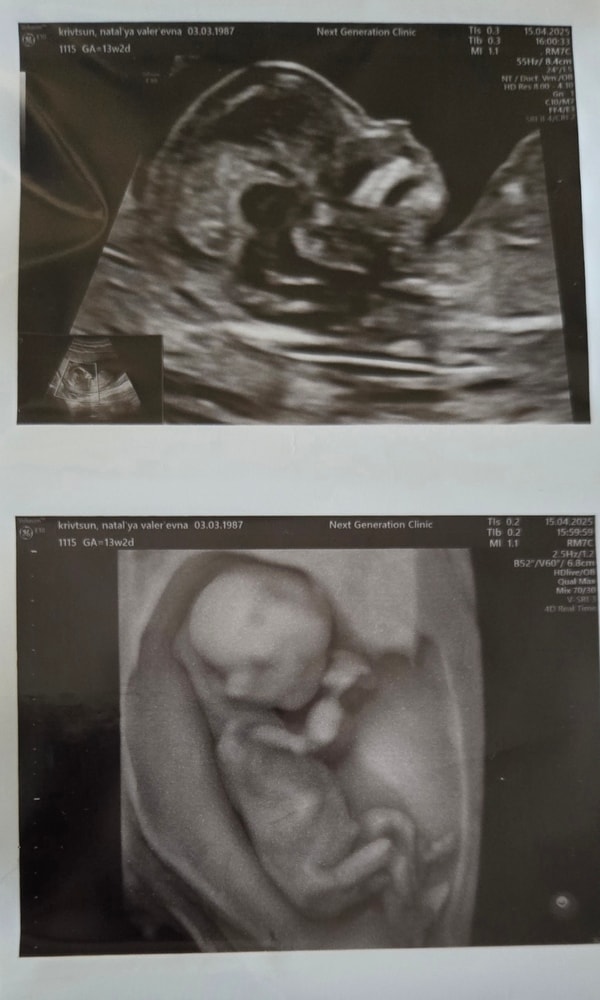

Всё о нашей беременностиВсем привет! Давно я ничего не писала. Мы растём и развиваемся. Прошли первый скрининг, все риски низкие, позужитель растёт, смотрели как машет ручками и ножками - это отдельное какое-то чудо.